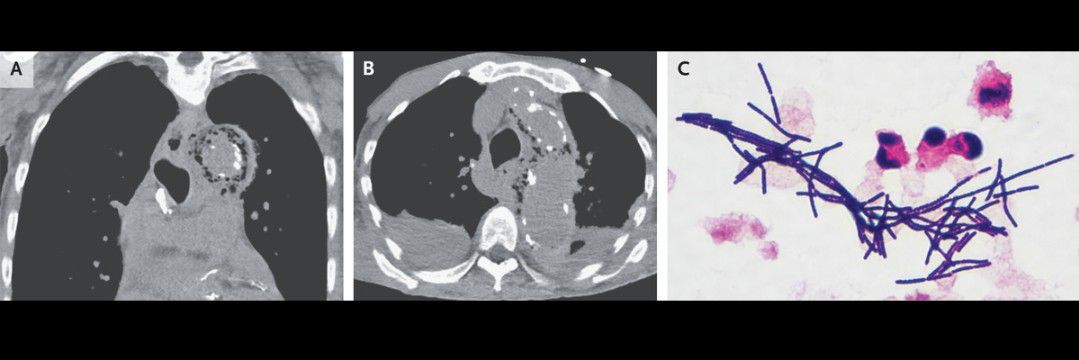

A 74-year-old man with a history of end-stage kidney disease and coronary artery disease, as well as a 3-day history of anorexia and generalized weakness, was brought to the emergency department for evaluation of decreased responsiveness during hemodialysis. On examination, he appeared ill and provided only brief responses to questions. A chest radiograph showed a widened mediastinum. Computed tomography of the chest, performed without the administration of intravenous contrast material, showed intramural gas in the ascending and descending aorta and aortic calcifications (Panels A and B). Gram’s staining of samples obtained from anaerobic blood cultures showed gram-positive rods (Panel C), and there was subsequent growth of Clostridium septicum. A diagnosis of infectious emphysematous aortitis was made. C. septicum infection is strongly associated with gastrointestinal cancer. The organism is thought to enter the bloodstream from the gastrointestinal tract; in cases of endovascular infection, such as that seen in this patient, it seeds atherosclerotic plaques. Three years before the current presentation, the patient had positive results on fecal immunohistochemical testing, but he declined colonoscopy. Abdominal imaging performed during the current hospitalization showed no overt signs of cancer. Intravenous penicillin G and clindamycin were administered. Although surgery is considered to be the definitive treatment for this type of infection, the level of risk was determined to be unacceptable in this case. The patient died on hospital day 7 while receiving comfort care.